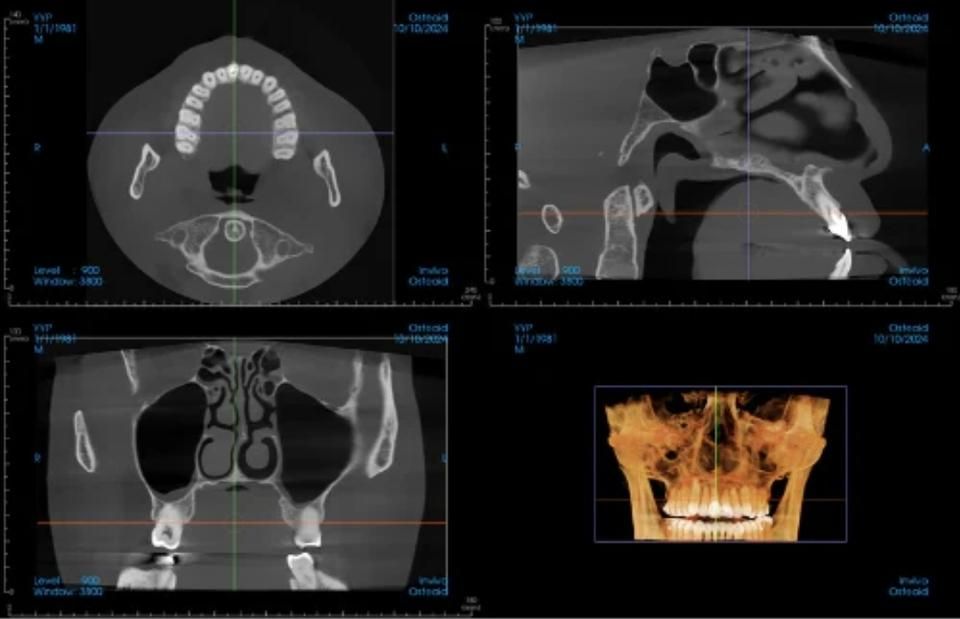

Advanced 5D Imaging

At Hoffman|Stone, we've invested in the most advanced dental imaging technology available today. By combining three sophisticated scanning systems, we create a complete 5D patient avatar that allows us to plan, visualize, and execute treatments with unprecedented precision. This technology transforms how we diagnose conditions, design treatments, and communicate with our patients—ensuring predictable, optimal outcomes for dental implants, full-mouth rehabilitation, and complex restorative procedures.